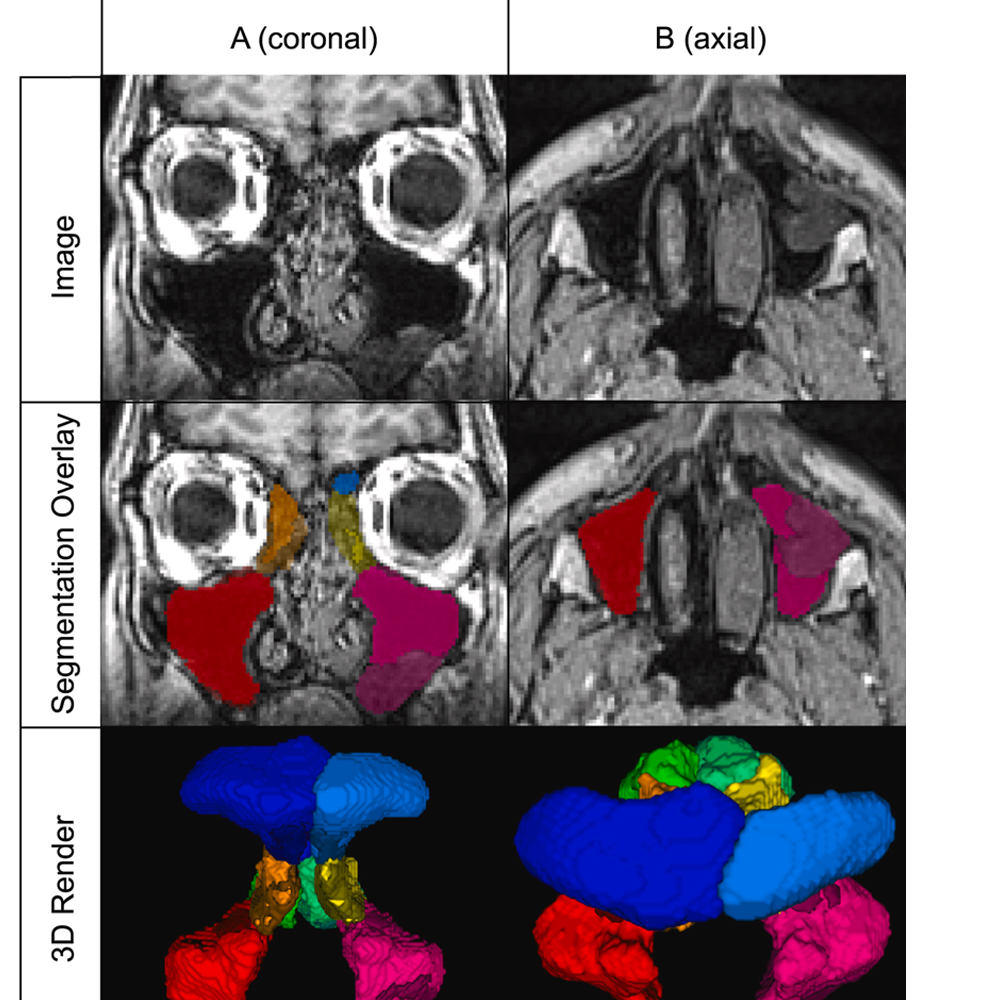

PARASIDE Enables Automated MRI Sinus Analysis

Researchers from the Menze Lab contributed to PARASIDE, the first fully automated T1-weighted MRI tool for whole paranasal sinus segmentation and disease scoring. The system enables objective, radiation-free assessment of chronic rhinosinusitis severity.